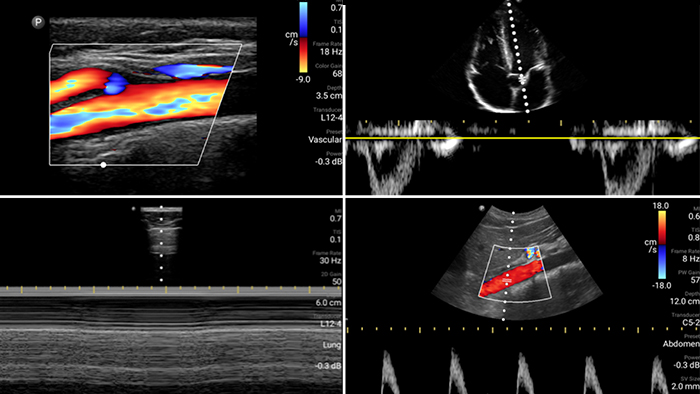

Evaluate, diagnose and treat your patients in minutes with a multi-point POCUS exam.

Lumify can help assess patients faster and improve accuracy when diagnosing common causes of dyspnea and other lung conditions.

Every second counts in cardiac care

Heart attack patients need immediate care. Lumify's cardiac presets can help patients get diagnosed faster to improve their outcomes.

• 4 to 1 MHz extended operating frequency range • 2D, color Doppler, M-mode, advanced XRES and multivariate harmonic imaging • High-resolution imaging for abdominal and cardiac applications: Cardiac, OB/GYN, Lung, Abdomen and FAST imaging preset optimizations Lumify aids life-saving technology in prehospital setting